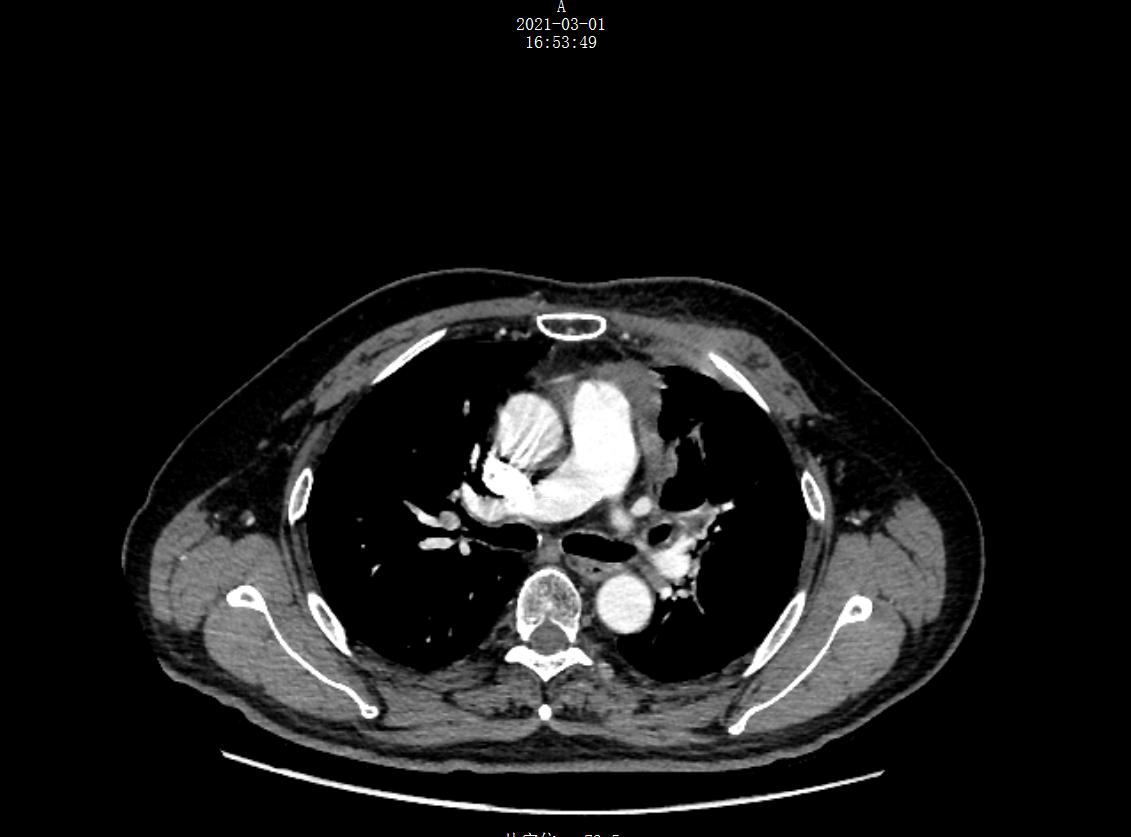

放疗结束后17个月(2021年2月)复查影像学,未发现局部复发与远处转移,左纵隔病灶及转移淋巴结仍持续缩小中